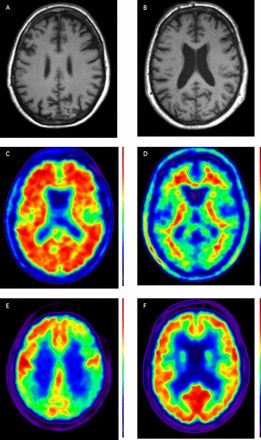

In practice, combining several of these different biomarkers, each of which provides different insights into the underlying disease process, may increase diagnostic certainty (see Case Study figure 1).

<img class="highwire-fragment fragment-image" alt="Figure 1" src="http://jnnp.bmj.com/content/jnnp/85/12/1426/F1.medium.gif" width="261" height="440"/>

Figure 1

Case showing clinical use of biomarkers. A 56 year old patient presented with a 5–10-year history of ‘scattiness’. Three years ago she developed difficulties reading an analogue clock, her spelling had declined and she had difficulty reading, losing her place from line to line. She received a clinical diagnosis of posterior cortical atrophy. Subsequently episodic memory became impaired. At the time of scanning, the Mini-Mental State Examination score was 19/30. A T1 volumetric MRI of the brain demonstrated a posterior pattern of cortical atrophy (A) with preserved hippocampal volumes compared with a healthy control patient (B); A 18F-florbetpair amyloid positron emission tomography (PET) scans shows widespread cortical amyloid deposition (C) compared with a healthy control (D) fludeoxyglucose (18F) PET scan demonstrates a posterior dominant pattern of hypometabolism (E) SUVR 1.0–1.4, compared with an age matched healthy control (F) SUVR 1.0–1.5. Cerebrospinal fluid examination demonstrated an elevated t-tau: 1080 pg/mL (NR 146–595); Aβ1–42 360 pg/mL ((NR 627–1322) giving a tau/Aβ1–42 ratio of 3. This case illustrates how different biomarkers can provide complementary information including regional neuronal loss, more widespread metabolic dysfunction, as well as confirming the underlying pathology—in this case, Alzheimer's disease. (NB for clinical purposes, 18F-florbetapir images should be interpreted on a grey rather than colour scale.)